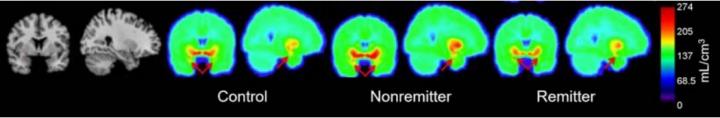

The PET tracer 11 C-DASB targets the serotonin transporter protein (5-HTT) in the amygdala of the brain, which is important for emotional processing. The drug escitalopram, a selective serotonin reuptake inhibitor (SSRI), can be an effective MDD treatment, but not for all patients. A PET scan with 11 C-DASB can indicate which patients will benefit by measuring the level of 5-HTT present before treatment.

For the study, 31 healthy individuals (controls) and 26 medication-free patients with MDD received a PET scan using 11 C-DASB. MDD subjects then received eight weeks of standardized therapy with escitalopram. The researchers found a significant difference in amygdala binding, with medication-free patients showing an 11percent lower amygdala binding than controls. These results suggest 5-HTT amygdala binding should be examined further, in conjunction with other measures, as a potential biomarker for remission following standardized escitalopram treatment.